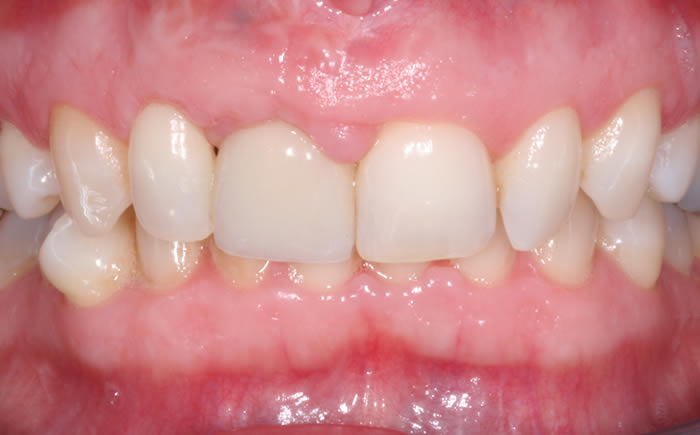

More front teeth replaced by dental implants

Case Three (4 images)